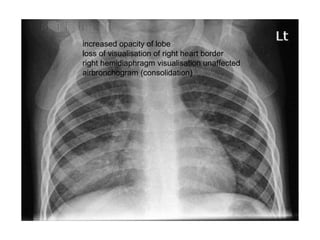

RML

increased opacity of lobe

loss of visualisation of right heart border

right hemidiaphragm visualisation unaffected

airbronchogram (consolidation)